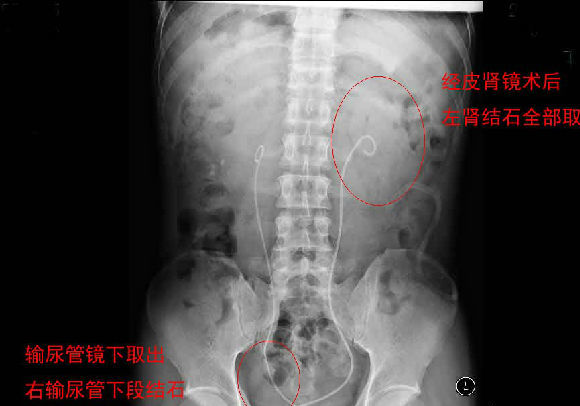

每天早上手術(shù)間響起泌外醫(yī)生們特有的交談聲音和機(jī)器們互相的運(yùn)轉(zhuǎn)聲交替成了一道熟悉不變的旋律,從手術(shù)室護(hù)士擺著各種專用體位,推著各種器械,液體進(jìn)進(jìn)出出,醫(yī)生們應(yīng)用著各種碎石手段消滅石頭,利用氣壓彈道、激光、超聲等碎石工具,把結(jié)石擊碎取出,一陣忙碌的節(jié)奏。泌尿外科的手術(shù)時(shí)間都不長(zhǎng),每天手術(shù)例數(shù)又多,你就會(huì)看見(jiàn)這么一群人來(lái)來(lái)回回,醫(yī)生護(hù)士還是那么個(gè),病人都換了無(wú)數(shù)。最長(zhǎng)一次從早上8點(diǎn)到隔天凌晨2點(diǎn)才結(jié)束手術(shù),回到家就立馬睡覺(jué)都顧不上吃飯?,F(xiàn)在手術(shù)間正做著一臺(tái)經(jīng)皮腎鏡下碎石取石術(shù),這是我們醫(yī)院泌外科的王牌。

經(jīng)皮腎鏡取石術(shù),就是在腰部建立一條從皮膚到腎臟的通道,通過(guò)這個(gè)通道把腎鏡插入腎臟,英文簡(jiǎn)寫為PCNL。經(jīng)皮腎鏡取石術(shù)是腎結(jié)石治療的現(xiàn)代微創(chuàng)技術(shù),我院在惠州率先開(kāi)展此項(xiàng)技術(shù),現(xiàn)在每年進(jìn)行數(shù)百例手術(shù),基本上已經(jīng)淘汰了開(kāi)放手術(shù)取石。經(jīng)皮腎鏡取石術(shù)是一項(xiàng)技術(shù)性非常強(qiáng)的手術(shù)。我們知道,腎臟是血管非常豐富的器官,腎臟血流占心臟排出血量的1/4。既要盡量避免出血、又要努力取凈結(jié)石、還要保護(hù)腎臟功能,這需要非常精細(xì)的手術(shù)技術(shù)。從某種程度上說(shuō),這個(gè)手術(shù)要比治療腎癌的腎切除術(shù)難度大很多。傳統(tǒng)的“開(kāi)刀取石”的方法,需要在腰部做一個(gè)的大切口,切開(kāi)腰部的肌肉,把腎臟分離出來(lái),在腎盂或腎實(shí)質(zhì)切開(kāi)一個(gè)小口,將結(jié)石取出來(lái)。這種方法損傷大、出血較多、痛苦重、恢復(fù)慢。通常手術(shù)后需要住院7天以上。因?yàn)槭中g(shù)切口大,不但皮膚不美觀,而且手術(shù)后患者的體力受影響比較大。與開(kāi)放手術(shù)相比,經(jīng)皮腎鏡取石術(shù)具有損傷小、痛苦輕、取石徹底、恢復(fù)快等優(yōu)點(diǎn)。腰部的切口通常小,因?yàn)椴磺虚_(kāi)肌肉,不但不影響美觀,而且手術(shù)后對(duì)勞動(dòng)力幾乎沒(méi)有影響。手術(shù)后住院時(shí)間也明顯縮短。與腹腔鏡取石相比,經(jīng)皮腎鏡取石術(shù)對(duì)腎臟及周圍的結(jié)構(gòu)影響小,不影響以后的各種腎臟手術(shù)。與體外碎石相比,它的治療周期短、效果立竿見(jiàn)影,對(duì)腎功能的影響也較小。(手術(shù)室/麻醉科 阮伊莎)